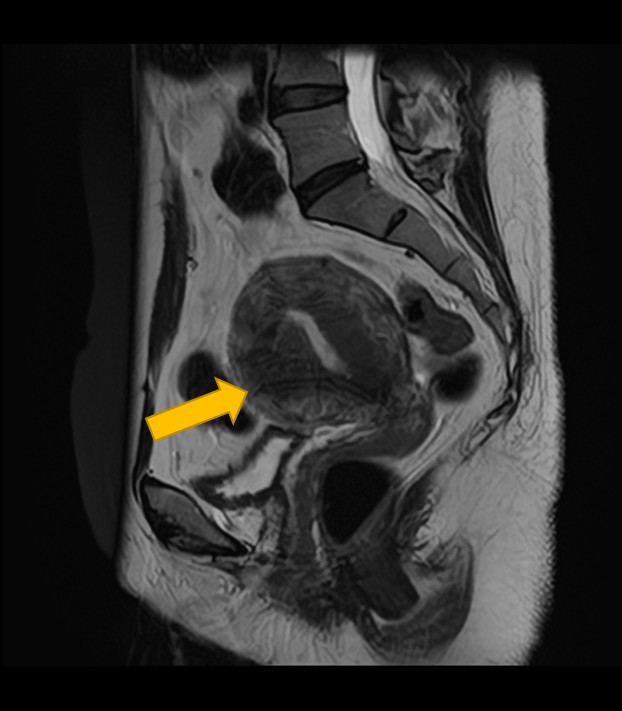

4. 子宮体がん・子宮頸がんの進行度診断

がんの大きさ、子宮筋層への浸潤度合い、子宮の周囲への広がり、さらにはリンパ節転移や遠隔転移の有無まで多角的に評価し、病期診断に貢献します。

| 子宮体がん・ 子宮頸がん | 腫瘍の大きさ、子宮筋層への浸潤度、周囲への広がり、リンパ節転移や遠隔転移の有無、病期診断。 |